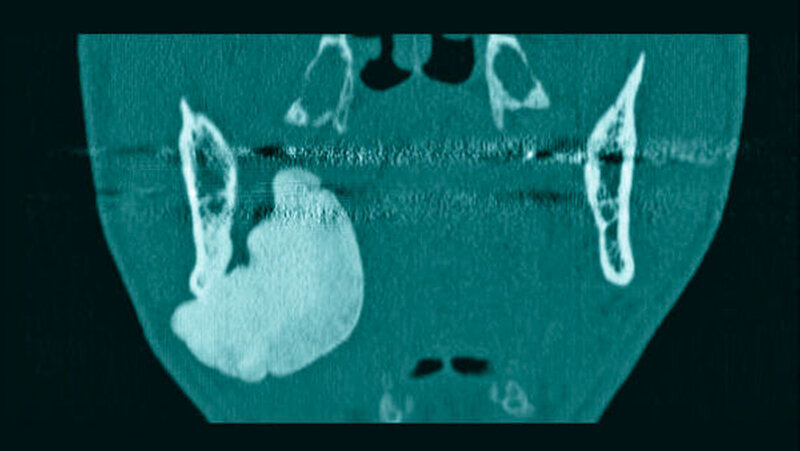

Im mitgebrachten alio loco erstellten Orthopantomogramm war eine gut abgrenzbare, ovale, homogene Verschattung zu sehen, welche sich im Bereich des rechten Kieferwinkels, in dorsaler und kranialer Richtung über diesen hinaus sowie im Bereich des aufsteigenden Unterkieferastes bis kaudal unter die Incisura semilunaris erstreckte (Abbildung 1). Computertomografisch war ausgehend von der medialseitigen Corticalis des Angulus mandibulae rechts eine irregulär, angedeutet rundlich konfigurierte, glatt begrenzte knöcherne Raumforderung von circa 4,4 x 3,3 x 4,7 cm Größe zu sehen (Abbildungen 2 und 3). Diese führte zu einer Verlagerung der Anatomie, insbesondere zu einer Vorwölbung der rechtsseitigen Oropharynxseitenwand (Abbildung 4). Es bestanden keine Hinweise auf eine knöcherne Destruktion oder auf eine Lagebeziehung zu einem Zahn.